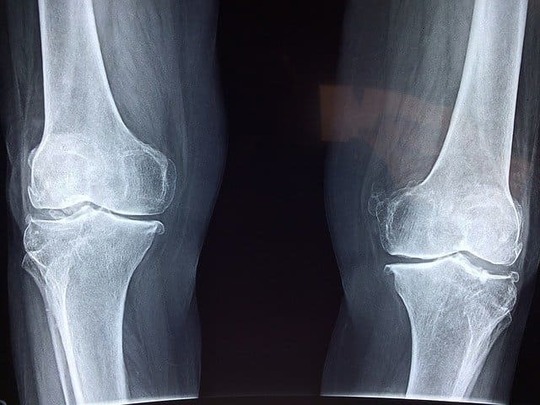

脱臼は、関節を形成している骨が完全に離れた状態のこと

脱臼は、関節を形作っている骨が完全に離れてしまった状態のことです。脱臼が起きると、骨と骨をつないでいる関節部分の骨が本来の位置からずれてしまうのです。

脱臼は程度によって、骨が関節から完全に離れた状態の完全脱臼と部分的に骨が関節から離れていて完全に離れている状態ではない亜脱臼に分けられます。

一般的に脱臼が起きる部位は腕や脚、顎や首、脊椎、肘や股などです。脱臼した部位には痛みや腫れが起こることが多く、あざやゆがみや曲がり、ずれなどが起こることもあります。